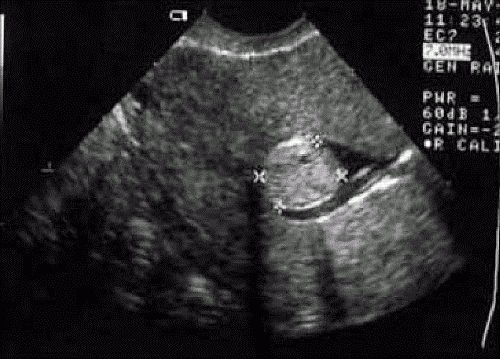

Миома матки часто протекает бессимптомно, что иногда приводит к позднему обращению за медицинской помощью, особенно если пациентка игнорирует профилактические осмотры. Заболевание может прогрессировать с развитием осложнений. Поэтому ранняя диагностика так важна.